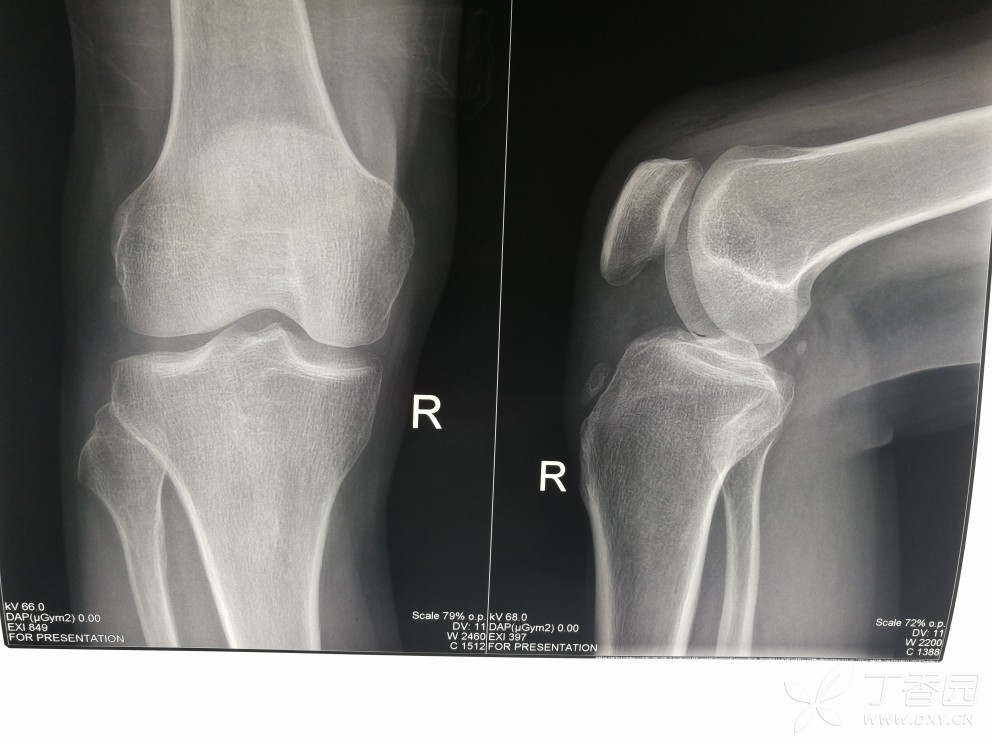

【请教】膝关节片上的这些钙化影是什么的钙化?

是韧带钙化?还是什么?胫骨结节的话,应该靠下吧